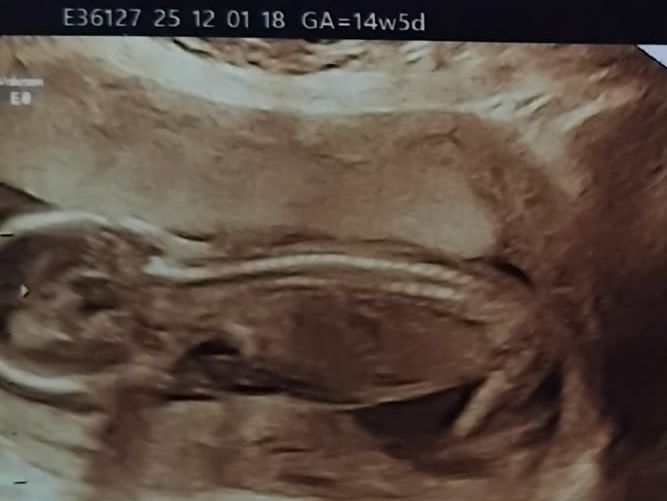

File: IMG-20251204-WA0001~2.jpg (33 KB, 667x501)

33 KB

33 KB JPG

I don't know this guy, I've never talked to him but I know his name and place: Jantikarn, from Delhi. He is today in Zirakpur, close to Chandigarh, for I don't know for how long, visiting his gf, a thai girl who is called by her coworkers "Jenny" who went to work there from Thailand. Since September, when she arrived to the hotel Bansal Easy, she is keeping a horny relationship with an indian guy from there and is currently pregnant from him, pict attached. She told her boyfriend (Jantikarn) she is pregnant, but she is making him think is his baby, and he is taking the responsibility. He doesn't know his gf is having an affair, he doesn't know the child is not his. At least 2 other girls who are staying with Jenny knows about it, but they are keeping the secret. Is that a "girl code"? Is because they are forced to live together they can't "betray" between them? I don't know